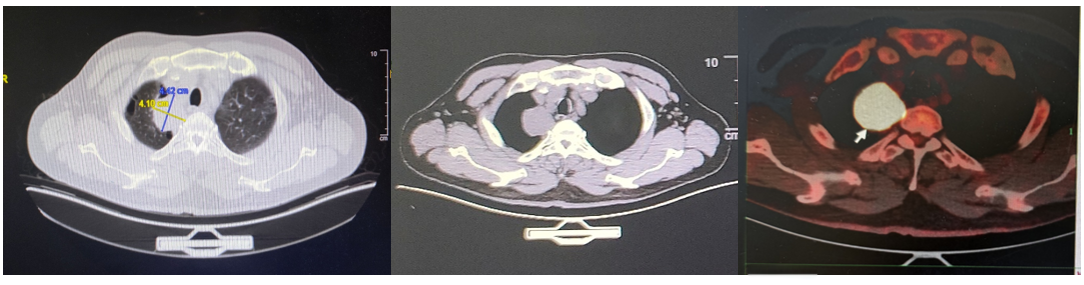

胸部CT+PET/CT(2023年5月17日):右肺尖叶占位,范围约4.4*4.1cm,FDG高代谢,恶性肿瘤可能大;伴周围炎;全身多发骨转移,右侧淋巴结转移,纵隔、腹膜后、两侧髂血管旁、左侧臀肌间隙淋巴结转移可能。鼻咽部炎症可能;左上肺少许纤维灶;两上肺肺气肿;食管下段炎症可能;肝囊肿。

PET/CT(2023年5月17日):骨盆多处骨质破坏,右侧髂骨为甚(骨病灶尺寸:6 cm* 4.5cm),周围伴软组织肿块,放射性浓聚。此外,骨骼多处放射性摄取增高。ECT示全身多发骨转移,左侧前肋(约第一肋骨)、腰椎、右侧骶髂关节、右侧耻骨、左侧髋关节为著。

图2. 原发灶与骨转移灶对比

(骨转移灶图左,中为PET/CT,右为骨转移病灶示意图)